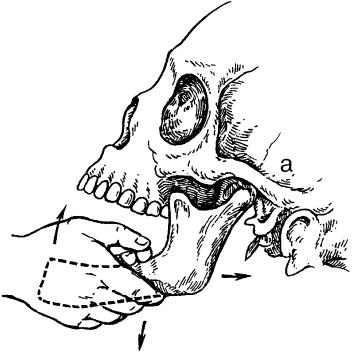

Хирургические действия, не связанные с разъединением тканей (например, вправление вывиха нижней челюсти), не входят в компетенцию оперативной хирургии (рис. 13, 14).

Рис. 13. Вправление вывиха нижней челюсти без разъединения тканей (направление смещения нижней челюсти обозначено стрелками). а – височно-нижнечелюстной сустав.